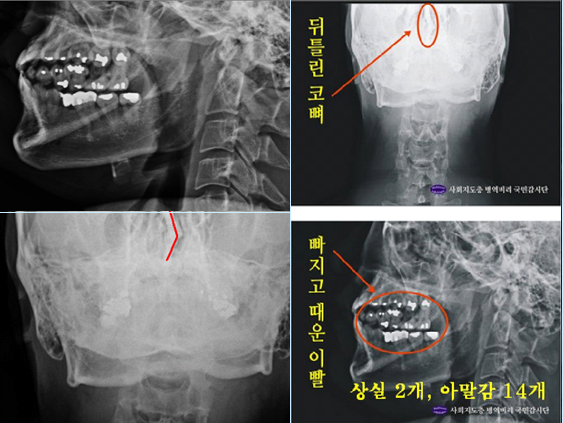

- ▲ ▲ 박주신 엑스레이(X-RAY)에 대한 치의학 박사의 분석자료.ⓒ 뉴데일리DB

▲ 박주신 엑스레이(X-RAY)에 대한 치의학 박사의 분석자료.ⓒ 뉴데일리DB

주신씨 구외 X-Ray 사진을 보면, 치아 상태가 매우 불량하다는 사실을 알 수 있다.

치아 2개는 아예 없고, 아말감으로 때운 치아가 무려 14개에 달한다.아말감(Amalgam) 치료는 여러 가지 단점을 갖고 있어 사용빈도가 크게 줄고 있다는 것이 치과의료계의 공통된 평가다.

치아의 치료상태는 매우 불량하고, 심지어 골반 X-Ray 사진에서는 골절된 뼈조각까지 발견됐다.주신씨의 것으로 알려진 치아 X-Ray 사진을 본 치의학 박사 C씨의 소견이다

“자료를 보면 2개의 이빨은 아예 없고, 아말감으로 때운 치아 14개가 보인다.

게다가 환자는 하악 1소구치(아래 어금니 앞쪽)까지 아말감으로 치료했다.

(젊은 사람이) 이런 경우는 매우 드물다.”“특히 전체적인 치료 상태를 보면, 소위 말하는 [야매]로 했을 가능성이 높다.

최근 국내에서 교육받은 치과의사의 치료라고 생각할 수 없을 정도다.

45번, 46번 보철 치료 및 치아 상실 문제에 있어서도 마찬가지다.

보철물로는 상당히 저렴한 비귀금속 합금을 사용한 것으로 보인다.

37번 치아는 아예 없는 상태로 방치하기도 했다.”“박주신의 가정환경을 고려하면, 이런 치료를 받았을 가능성은 1%도 안 된다.

서울 방배동에 거주했던 중산층 이상의 가정에서는 흔치 않은 상황이다.”